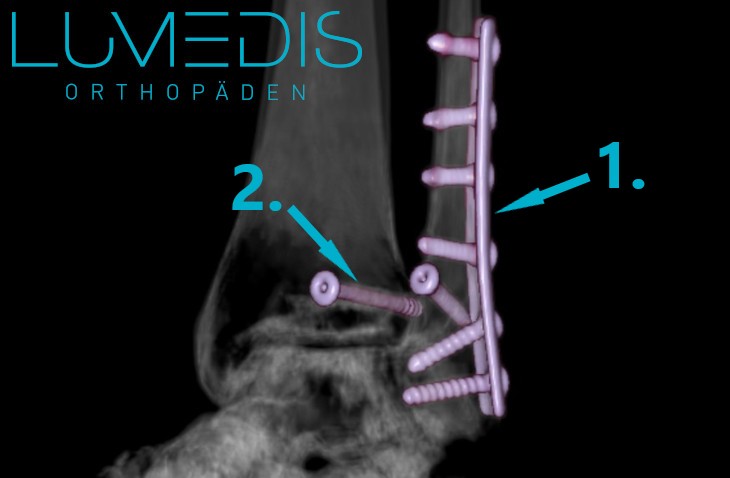

Röntgenbild eines Sprunggelenksbruchs mit Metallplatte und Schrauben

Die Therapie einer Weber B Fraktur ist in der Regel operativ. In Vollnarkose wird die Stelle des Bruchs eröffnet, die Bruchränder gerichtet und diese meistens durch Schrauben oder Platten fixiert, bevor die Haut wieder verschlossen wird.

Eine operative Behandlung einer Weber B Fraktur ist immer dann notwendig, wenn es sich um eine verschobene Fraktur handelt und wenn die stabilisierende Syndesmosen verschoben ist.

CT-Rekonstruktion einer Weber B-Fraktur